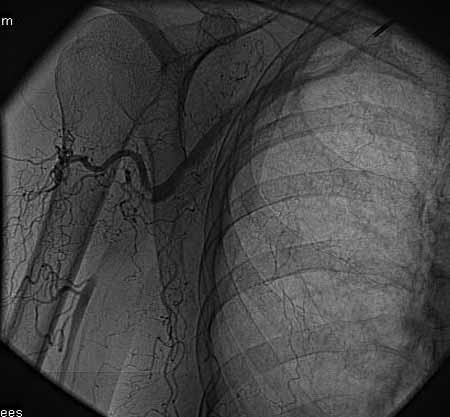

标题: DSA0091:肱动脉支架 [打印本页]

标题: DSA0091:肱动脉支架

女,66岁,右上肢无力.

馆主不错,图象清晰,栓塞处显示很清晰